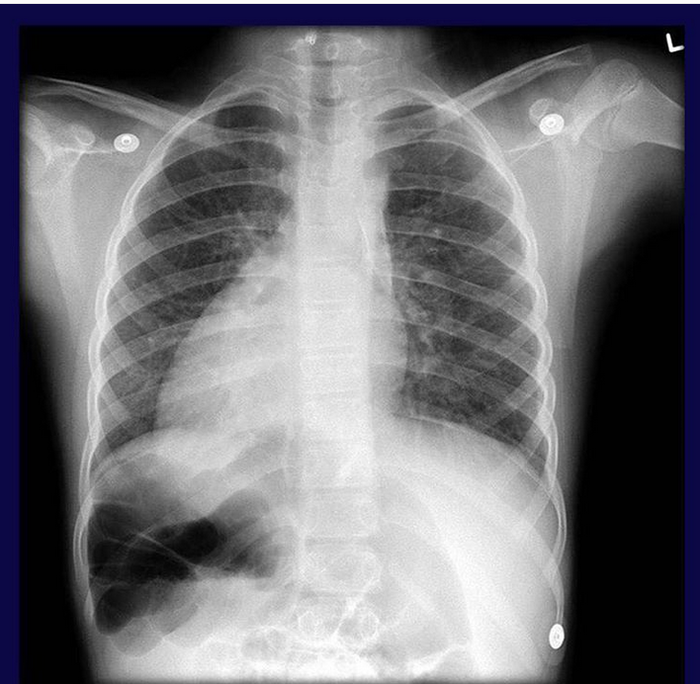

Такие случаи наверное бывали у всех реаниматологов. На фото автор Моторов Алексей.

Книжка вышла с той самой фотографией. И теперь всякий раз, когда я смотрю на обложку, я думаю о той женщине, что много месяцев, день за днем, отвоевывала свою дочь у смерти. Шестая койка, где лежала Наташа, в кадр не вошла, но я знаю, что мне, тому, на фотографии, сидящему между кроватью и столом, достаточно подняться, сделать несколько шагов и коснуться ее рукой.

1. На заднем фоне аппарат ИВЛ РО-6, до сих пор используется, иногда

Фото 2 - доклад на утренней конференции, 1985